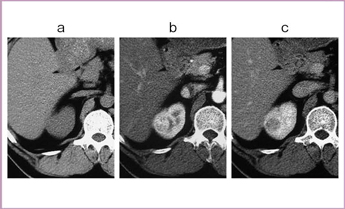

右腎の上局に,早期に造影効果を示す腫瘤が認められ,後期では抜けている(図6)。凍結治療時,MRIでは明瞭な低信号域として氷が描出される(図7)。MRIでは多方向からの撮像が可能で,完全に氷が腫瘍をカバーしているかを確認して治療を進めていくことができる。3週間後の造影CTでは,凍結部位の内部に造影効果が認められる特徴的な所見が得られた。RFの場合は,ほぼ完全に消えてしまうが,凍結治療では造影効果がいつまでも残る場合があり,その評価は今後の課題である。8か月後には,瘢痕組織が収縮していることが確認された。

外側に発育するRCCに対し,多方向からMRIを撮像して,凍結状況と腫瘍の関係を確認しながら凍結治療を行った。2週間後の造影CTでは,辺縁部に淡い造影効果が見られ,内側はしっかりマージンが取れており,治療は成功したと評価した。しかし,10週後に造影CTを行ったところ,早期の造影効果と後期での抜けが認められ(図8),辺縁部に残存腫瘍があることが確認されたため,再度の凍結治療を行った(図9)。MRガイド下の経皮的凍結治療は比較的安全に行えるため,繰り返し施行することが可能である。本症例では,1年後の造影CTで造影効果は完全に消失し,腫瘍部位も収縮していた。